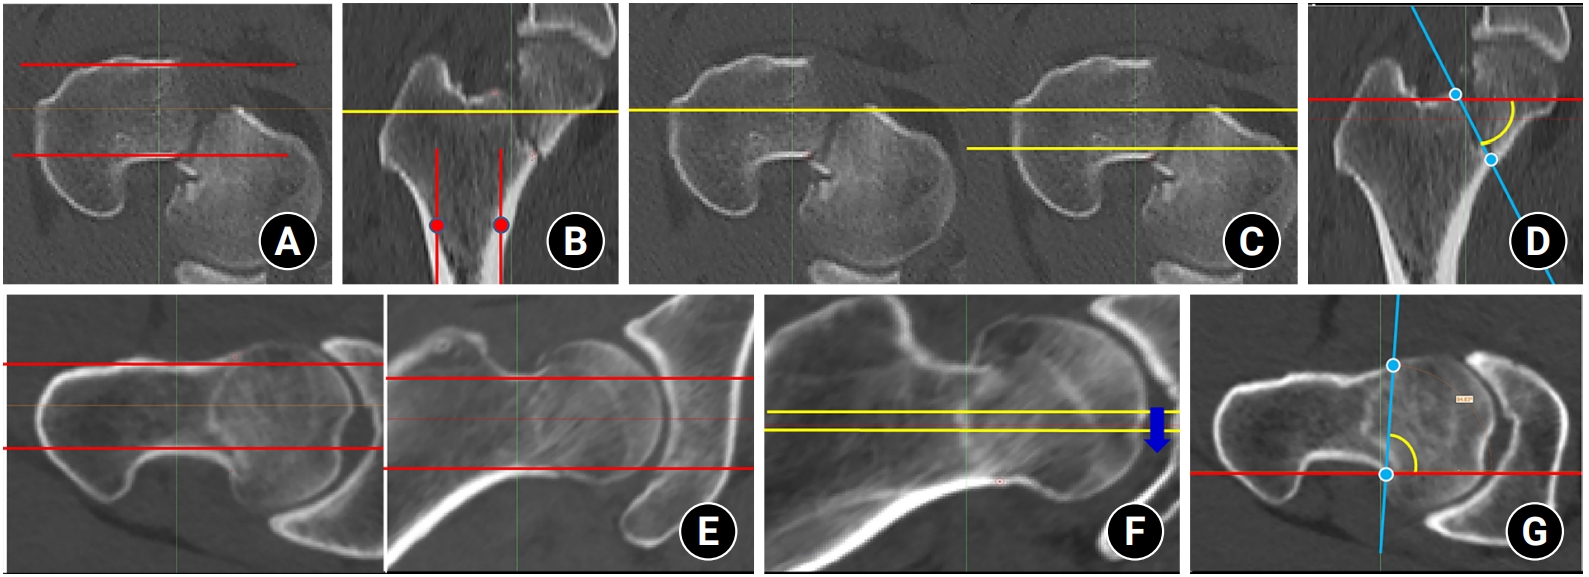

Data sources and measurement

Fig. 1.

After the proximal femur was selected as a cropping area, the scanning plane was reformatted parallel to the neck midline of the neck-shaft fragment in the axial plane. The proximal femur was then realigned vertically to the ground in the coronal plane using tools of Mimics software. Then, fracture morphologies were assessed in coronal (A), axial (B), sagittal (C), and three-dimensional biplanar plane (D).

Fig. 2.

To make consistent measurements and eliminate projection error, after the computed tomography scan plane was reformatted to an axial plane parallel to the femoral neck axis, red lines were placed anterior and posterior to the neck cortex in the axial (A) and coronal (B) planes. The yellow lines were placed in the centerline and posterior cortex (C). Then, (D) the coronal Pauwels angle (PA) was measured between the red line (ground line) and the blue line (reformatted fracture angle) in three consecutive images of the coronal plane. (E) The red line marked the anterior and posterior cortex in the axial and coronal planes. (F) The yellow lines were placed along the centerline of the neck, and three consecutive images of the axial plane were chosen. Then, (G) The axial PA was measured between the red line (ground line) and the blue line (reformatted fracture angle).